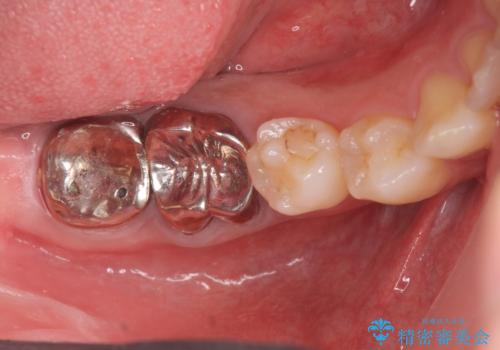

スペース狭小な銀歯を白くしたい 歯冠長延長術を併用したセラミック治療

- 「笑った時に目立つ奥歯の銀歯を外して白くしたい。」と希望され来院されました。

金属のクラウンは薄く加工しても壊れないことがメリットですが、セラミッククラウンを装着するにはスペースが少なすぎ、このまま治療を進めると外れやすく壊れ易いセラミッククラウンの設計となるため、歯周外科を行い狭小なスペースの拡大を行うこととしました。